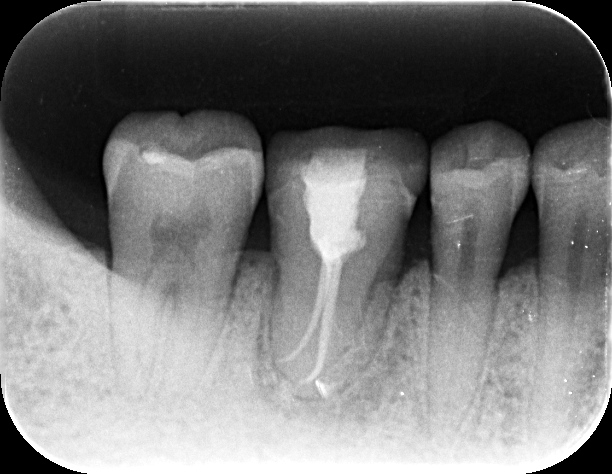

Finalセレックにて補綴

Finalセレックレントゲン